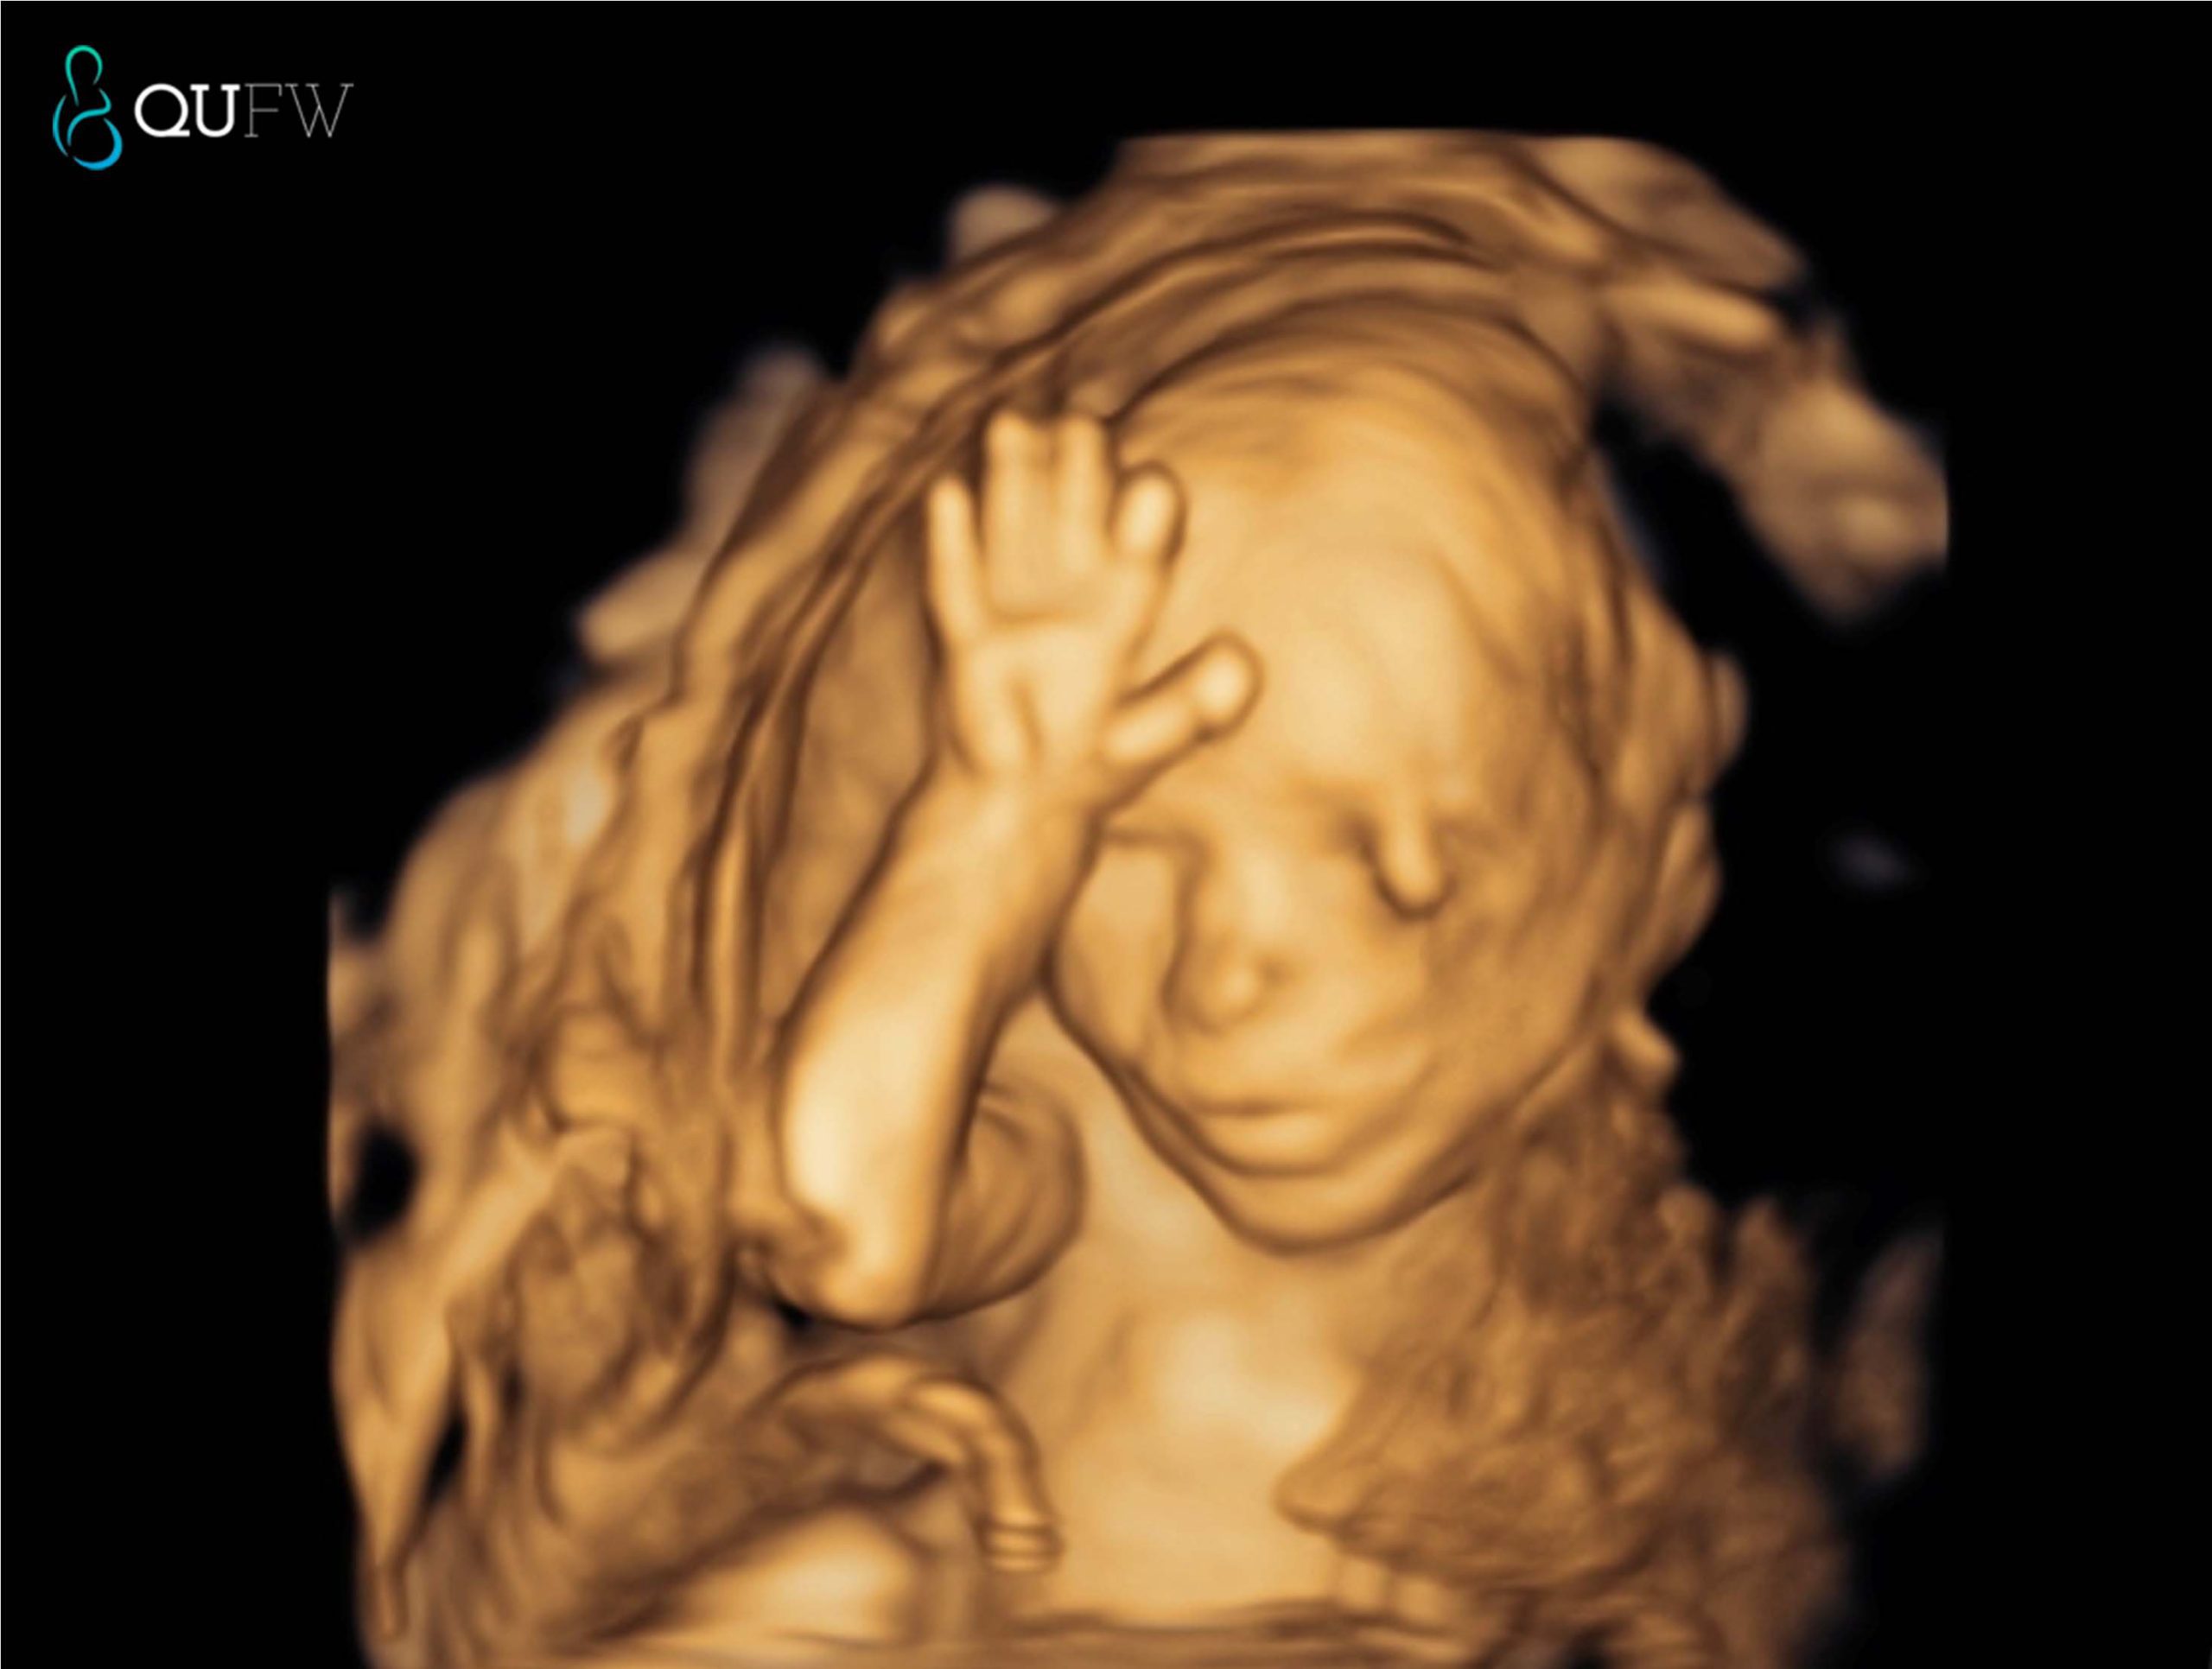

3D/4D Scanning

The majority of the scan is completed in conventional 2D (greyscale) as this offers the best resolution for detecting abnormalities. We will also try to obtain some images in 3D/4D of your baby, but this is very dependent on the baby’s position, the amount of amniotic fluid and maternal issues like placental position and maternal body habitus. The priority of the ultrasound is to check the baby’s well being and to provide you and your doctor with all the information we can in regards to the baby’s health. In reality, it may be difficult to obtain the ‘perfect 3D/4D’ image of your baby due to a variety of reasons. Our staff will make every effort to provide you with some keepsake images.

3D image of a 20-week fetus